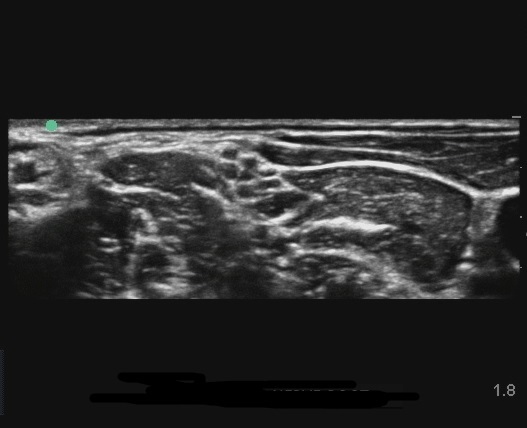

EDGE: Interskalenär